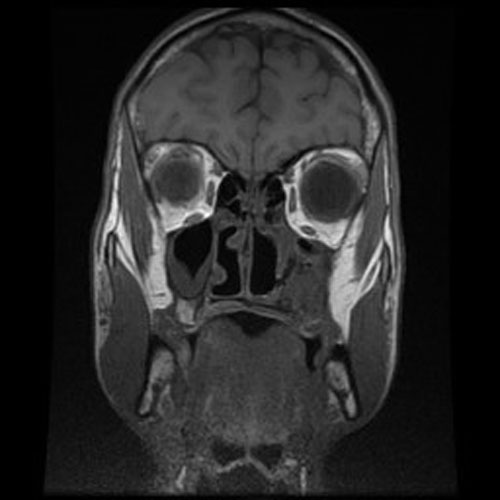

Clinical information: The patient was a 20 year-old man who was referred to this hospital because of a nasal mass. MRI revealed a poorly enhancing mass just posterior to the mucosa of the left maxillary sinus in the region of the pterygoid plates. An endoscopic biopsy was performed and yielded the current specimen. The followings are representative images:

MRI Coronal

Radiology of the Case: There is an expansile lesion in the left maxillary sinus that invades into the palate and alveolar ridge. This is an aggressive tumor.